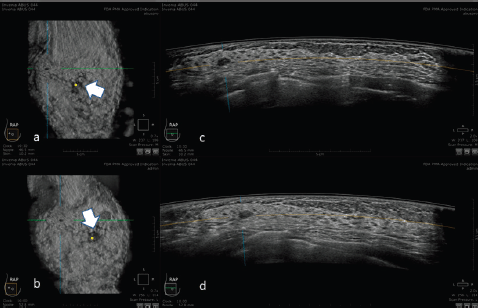

An example of the ABUS image is shown in Figure 1.

Figure 1. 3D ultrasound image at the dedicated workstation of a 82-year-old patient with biopsy proven ductal infiltrating carcinoma. a and b: reconstructed coronal plane; the lesion is marked as a reference point. Arrowhead shows the nipple. c and d: axial plane: the lesion is marked as a reference point. Arrowhead shows the nipple.